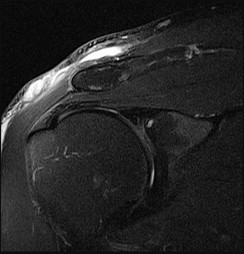

This patient has a dedifferentiated liposarcoma within a preexisting atypical lipomatous tumor. The imaging demonstrates a large fatty mass with increased internal septations proximally (the atypical lipomatous tumor) and a solid enhancing mass distally (the dedifferentiated portion). A biopsy reveals a high-grade liposarcoma. The other diagnostic responses do not reflect sarcomatous transformation of the lesion.